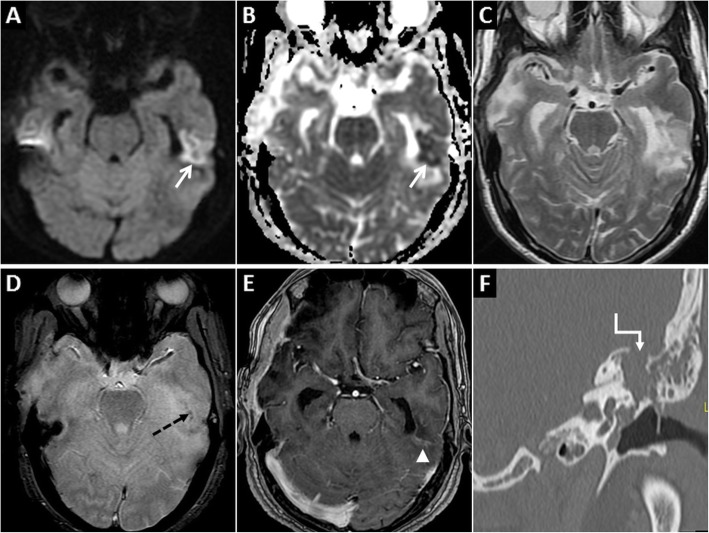

Fig. 1.

MRI of the brain performed in the acute phase of HIE. On axial DWI (a, d) and axial ADC images (b, e), symmetric GRD is seen in the perirolandic cortices (arrows in a and b) and in the visual cortices bilaterally (arrows in d and e). Restricted diffusion is also observed in the putamina (dashed arrows in d and e) and in the thalami (arrowheads in d and e). Corresponding axial T2W images (c, f) demonstrate no obvious signal abnormality in the cortices. However, there is mild T2 hyperintensity in the putamina (dashed arrows) and in the thalami (arrowheads) (f)

Fig. 2.

MRI of the brain performed in the subacute phase of HIE. DWI hyperintensity is noted in the deep grey nuclei and extensively in the cerebral cortices (arrows) on axial DWI image (a). There is no signal drop on axial ADC image (b). Diffuse cortical swelling and signal changes (arrows) are appreciated better on the axial T2W image (c). Minimal intraventricular blood (dashed arrow) is seen on axial GRE image (d). Axial source 3D-TOF MRA image (e) and reconstructed maximum intensity projection MRA image of Circle of Willis (f) show no flow signal in the intracranial arteries